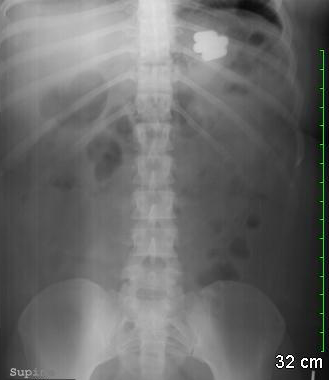

Radiografia abdominal simples revelando múltiplos corpos estranhos no lúmen estomacal

Do acervo de Juan Carlos Munoz